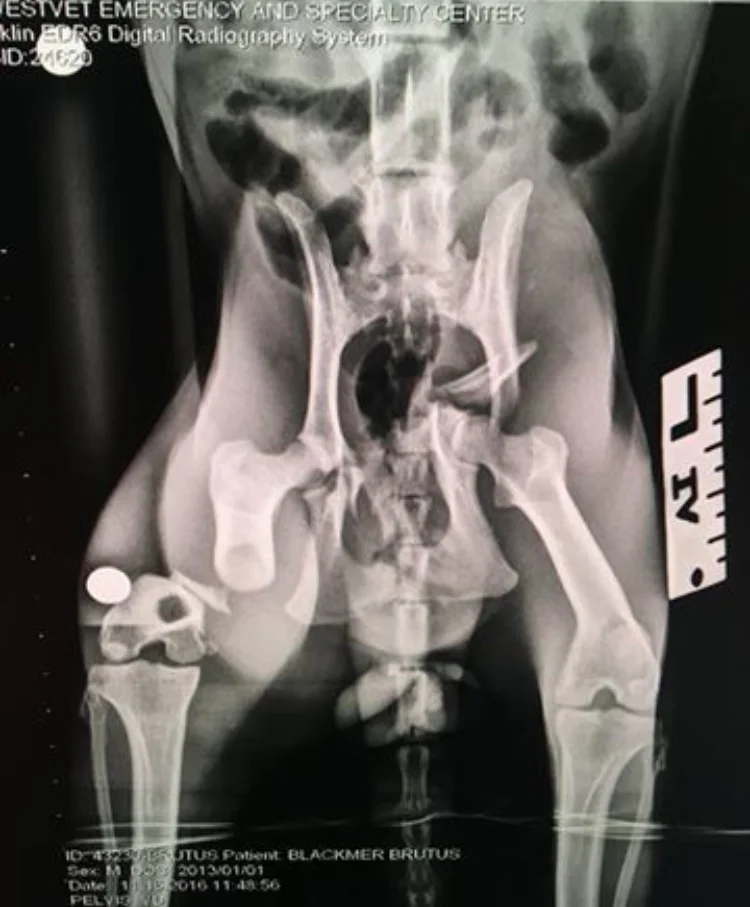

We have so many wonderful happy ending stories! We have to start however, with our first official kitty that was rescued from the lake here. His name is Fergus and he was a pretty sad guy when we found him. He had suffered a fractured pelvis and femur. It appeared from his x-rays that he had been in this condition for some time. It was winter and this poor guy had to attempt to survive this way and stay warm     It simply broke our hearts! We were able to raise funds to have his injuries surgically repaired and he has gone on to live the best life IMAGINABLE with three doggie siblings.